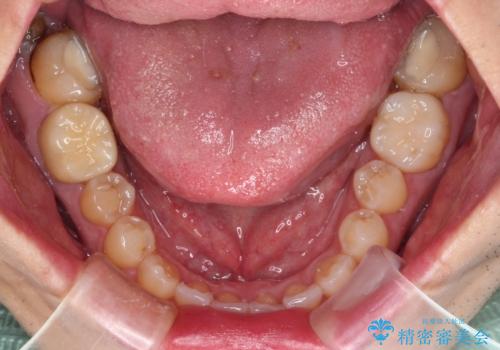

長期海外赴任が近いとのことで、出発に間に合うようにアポイントを調整して治療を進めて行きました。

中途半端に歯冠の見えている親知らずもあったため、そちらも出発前に抜歯を行いました。